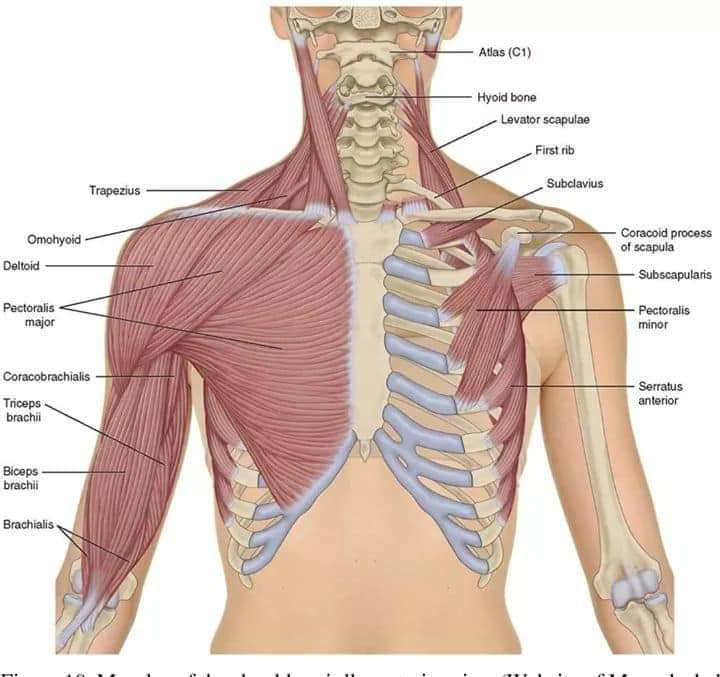

М'язова система людини є однією з основних систем організму, що відповідає за рухи, підтримання пози та стабільність. Вона складається з понад 600 м'язів, які можна класифікувати на скелетні, гладкі та серцеві м'язи. Скелетні м'язи, які є об'єктом нашого детального розгляду, дозволяють контролювати навколишній світ і виконувати різноманітні рухи. Особливу увагу в нашій статті буде приділено шейним і спинним м'язам, оскільки ці групи м'язів мають критичне значення для підтримання правильного постава та функціонування хребта.

Скелетні м'язи з'єднані з кістками за допомогою сухожиль і відповідають за більшість волевих рухів. Вони поділяються на:

- Швидкі м'язи - призначені для швидких і потужних рухів.

- Повільні м'язи - забезпечують стійкі і довготривалі рухи.

Скелетні м'язи мають поперечну смугасту структуру, що забезпечує їхню здатність до швидкого і ефективного скорочення.